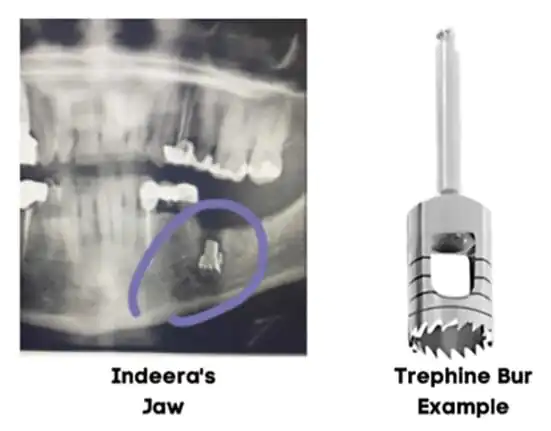

New details have emerged in the lawsuit filed against oral surgeon Kirk E. Scott, M.D., D.D.S., and Stonebriar Facial and Oral Surgery in Frisco. In the original suit, filed in April 2021, a Texas woman claimed the dental specialist left a metal drill bit inside her jaw, failed to tell her about it, and then minimized the incident when it was revealed to her in X-rays five months later. An amended complaint recently filed in Dallas County includes excerpts from a deposition where Dr. Scott admits he knew the drill bit broke inside of Indeera Musa’s jaw at the time of the procedure and failed to perform an X-ray, which would have verified the metal bur remnant.

In addition, the amended lawsuit claims Dr. Scott chose to keep the incident a secret by not telling anyone at his office and did not document it in Musa’s medical records, which negatively impacted her post-procedure care.

Within days of her surgery, Musa called Dr. Scott and Stonebriar Facial and Oral Surgery multiple times and returned to the medical office in advance of her scheduled follow-up visit because her jaw pain and swelling had become so intense despite following her post-operative instructions, according to the suit. Further, the suit states that Dr. Scott was aware of Musa’s continued complaints yet failed to communicate about the broken metal drill bit with another doctor or the surgical assistant at his office who saw Musa for post-operation appointments.